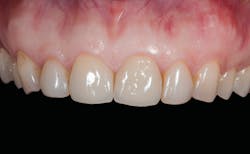

A patient presented with multiple deficient restorations, discolored teeth, and attrition (figures 1–4). The patient’s treatment plan was a full-mouth rehabilitation with a combination of veneers, crowns, and onlays.